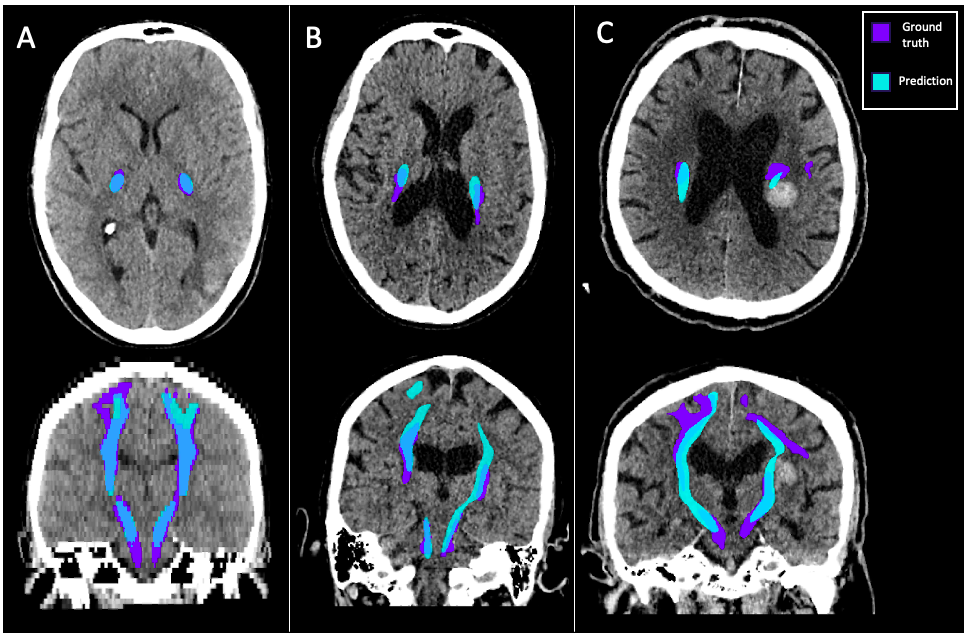

Inference was run over diagnostic CT scans from the MISTIE III clinical trial dataset, and predicted labels of the CST and haematoma were generated for 487 patients, three of whom are shown in Figure 3. Demographics of the MISTIE III trial, split by CST integrity, are described in Table 1.

Refer to caption

Figure 3: Three patients from the MISTIE III dataset with predicted CST and haematoma labels. A) A patient with a haematoma not involving the CST B) A patient with CST haematoma overlap but no split tract C) A patient with no CST haematoma overlap, but a split tract.

We observe ‘splits’, interruptions in the z-axis, in the tract where the network cannot detect white matter. It is hard to say whether a split in the predicted tract is a reflection of damaged or undetectable white matter, or a failing of the model close to the haematoma. However, the fact that the presence of a ‘split’ very significantly predicts outcome after stroke shows that this does give us valuable information about CST integrity. It could be that combining discontinuity in the tract segmentation, and overlap with the haematoma would give us a comprehensive overview of whether a patient has damage to the CST.